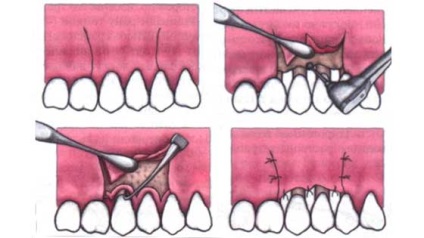

lambourilor este necesară atunci când parodontita severă și parodontita, atunci când pungile parodontale sunt prea adânci. Pentru a face acest lucru:

- Este o secțiune orizontală în zona gingiei, gingivală indepartezi de la o margine la o jumătate de milimetru. Această clapă - o fâșie subțire de țesut moale - eliminat, deoarece un astfel de țesut deteriorat niciodată nu va fi capabil să adere la dinte.

- tesutul gingival este jupuit de pe dinte, cu suprafața mucoasei interioare a dintilor - prea.

- Acumulate în pungile parodontale ale plăcii și a țesutului de granulație este îndepărtată, rădăcinile sunt lustruite.

- Gumele tensionat la gât de dinți și sunt reticulate. Suturile sunt suprapuse în spațiile interdentare).